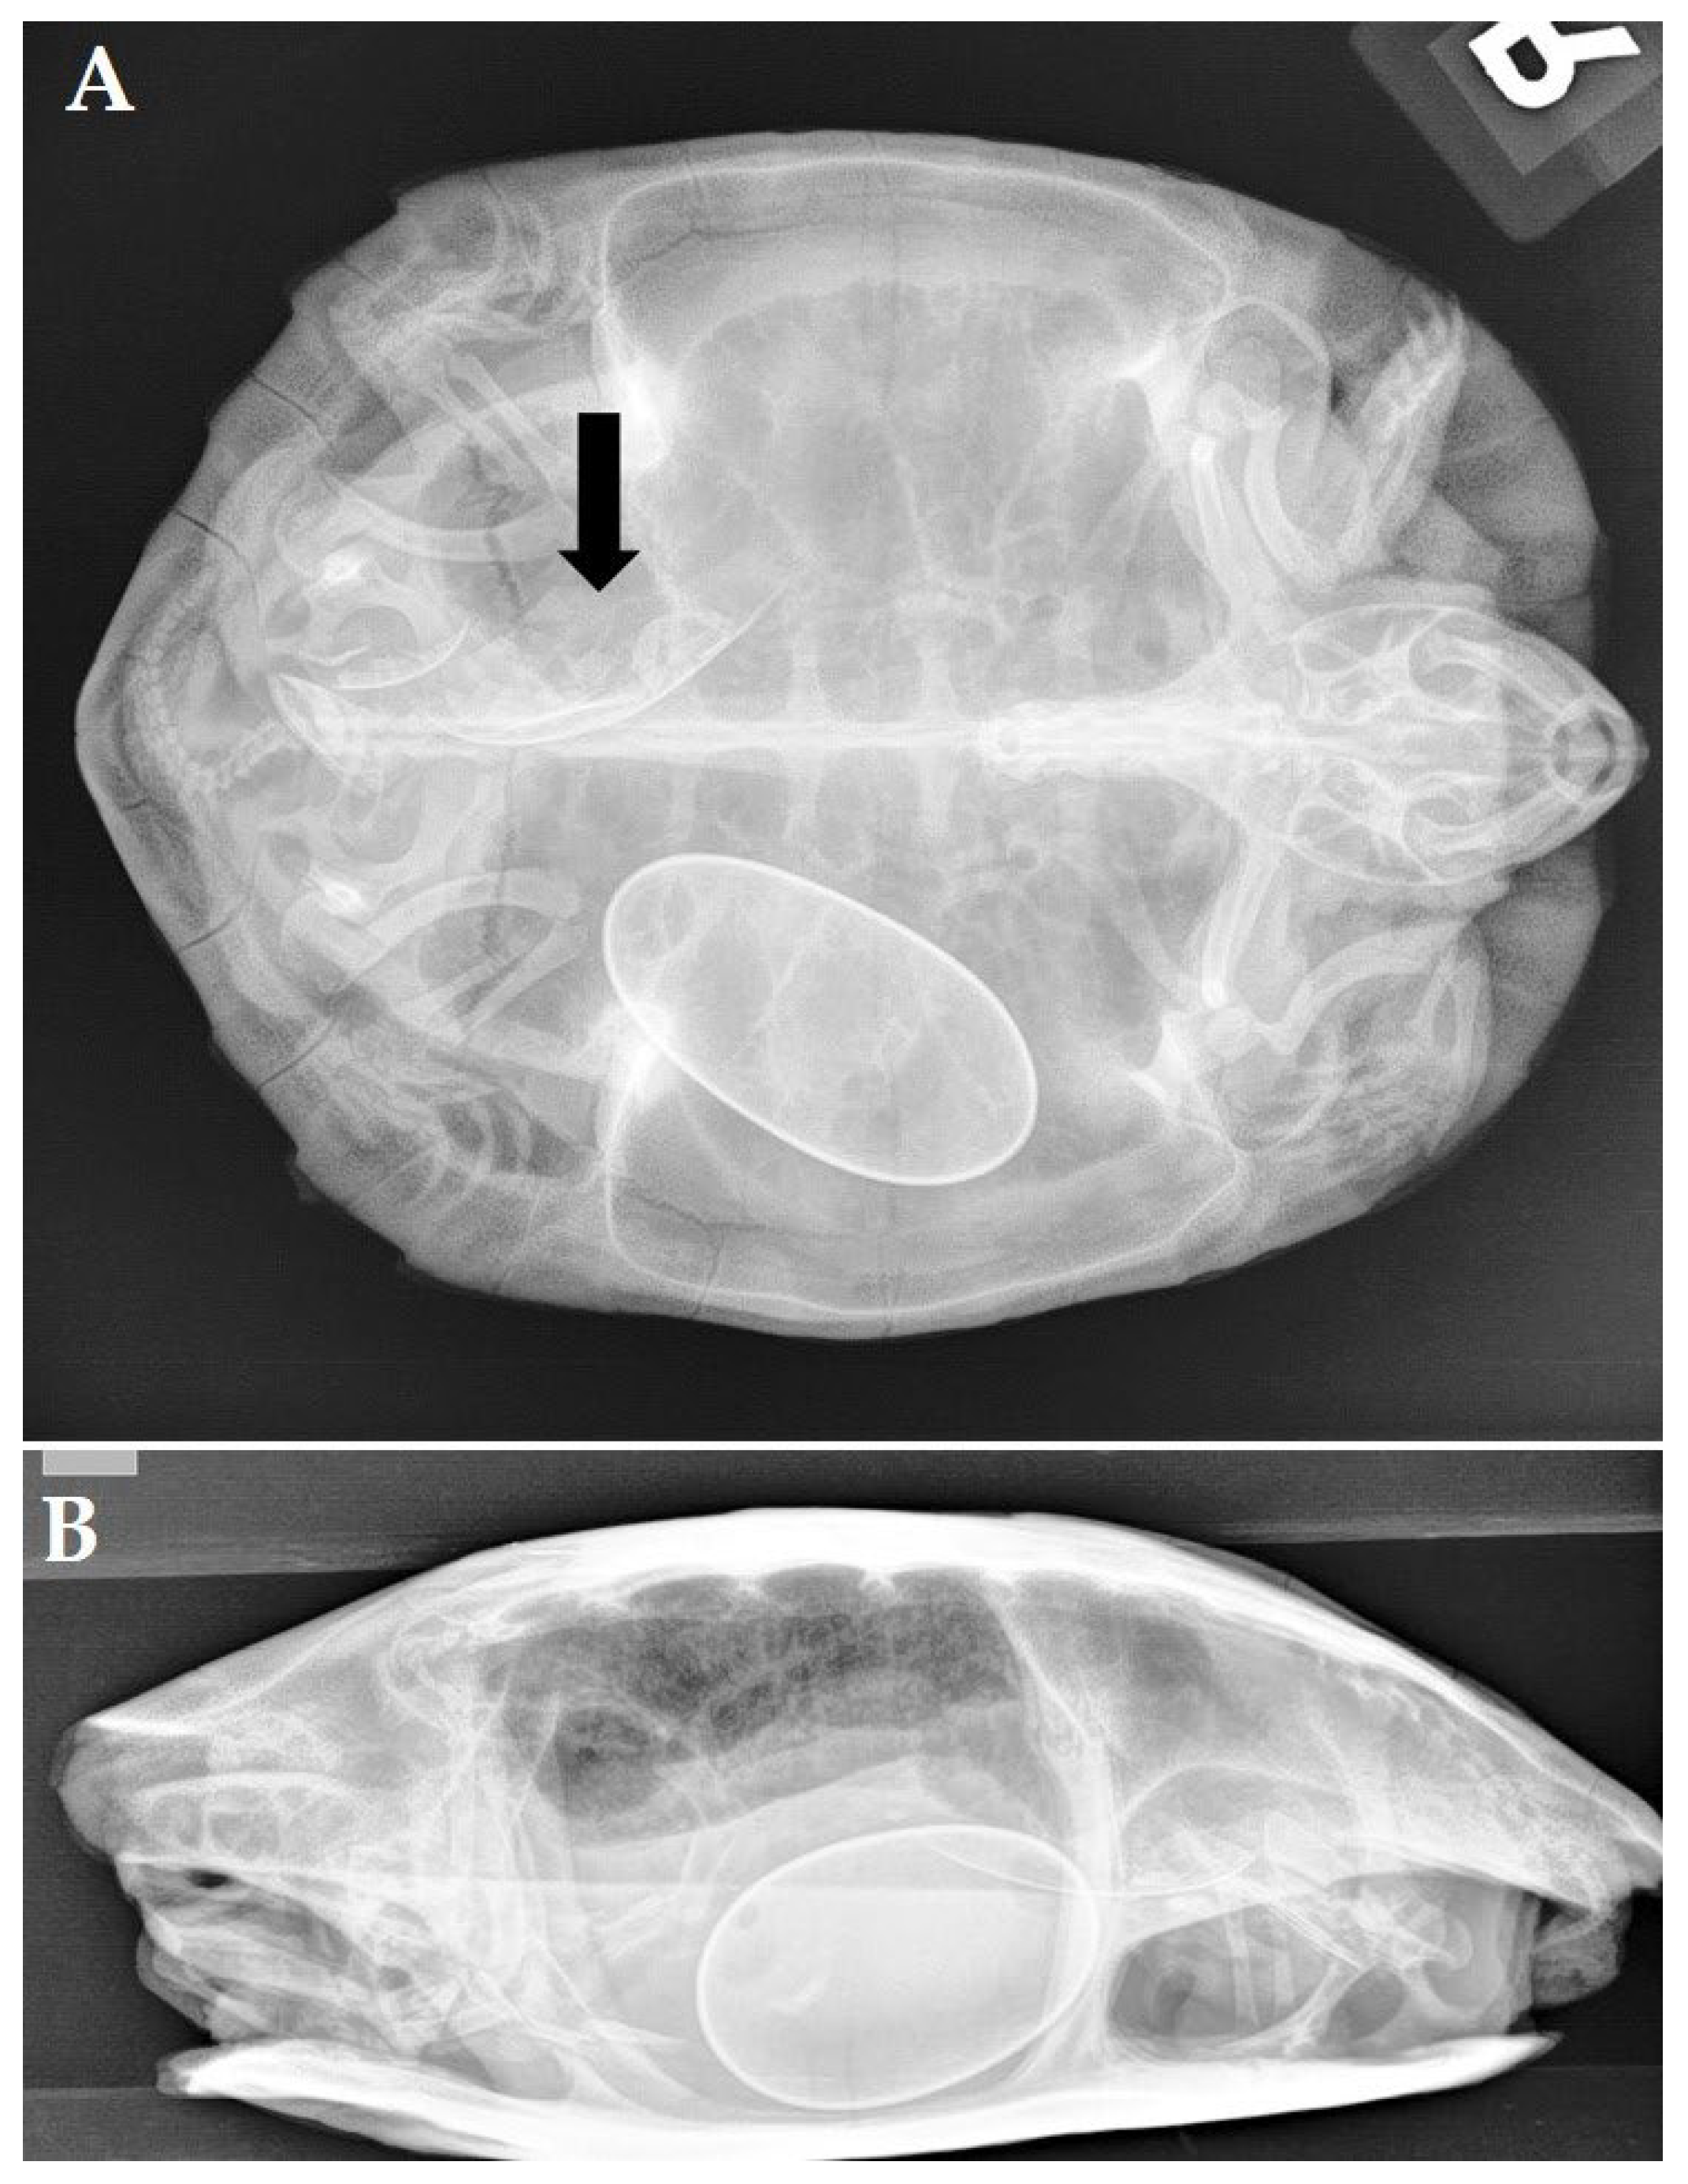

A 29-year-old female red-eared slider (Trachemys scripta elegans) was presented with anorexia and apathy after 2 weeks. During the past 22 years, the turtle annually produced 4 to 6 eggs and had no clinical history. Radiographic projections (Figure 1A,B) revealed the presence of 5 eggs located at the right side of the caudal coelomic cavity. Three eggs had an irregular shape, and one egg had an unusual small size and seemed to be fused with one of the other eggs. All eggs showed abnormally thickened shells, and a lamellar appearance was noticed in the most cranial egg. A generalized soft tissue opacity occupying the entire coelomic cavity was noted, causing obvious compression of the lung field on the laterolateral (Figure 1B) and craniocaudal projection. An ultrasound confirmed the presence of retained eggs and the presence of a large soft tissue mass measuring approximately 11.5 × 6.1 cm (Figure 1C) at the left-mid- to caudal coelomic cavity. The mass showed a heterogenic appearance, and a color doppler examination revealed pronounced vascularization. The latter findings yielded obstructive dystocia and chronic egg retention caused by a space-occupying mass.

Figure 1. Chronic egg binding associated with a scirrhous ovarian carcinoma in a red-bellied slider (Trachemys cripta elegans). (A) Dorsoventral radiographic projection: 5 eggs located at the right side of the caudal coelomic cavity. An irregular shape is noted in 3 eggs and all eggs show abnormally thickened shells with a lamellar appearance in the most cranial egg. One egg has an unusual small size and is fused with one of the other eggs (arrow). (B) Generalized soft tissue opacity of the coelomic cavity with obvious compression of the lung field on the left laterolateral projection. (C) Postoperative view after removal of the ovarian neoplasia and retained eggs. (D) Histological section of a scirrhous ovarian carcinoma (Hematoxylin and eosin stain) composed of a cell-rich tissue that is growing infiltrative in dense collagen stroma. Neoplastic cells are organized in islets to multi-layered tubules.